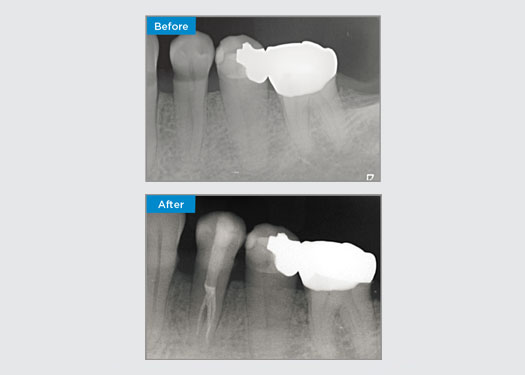

Casos clínicos

Los médicos de todas partes de Australia y Nueva Zelanda comparten amablemente presentaciones relevantes, interesantes y, a veces, desafiantes para los pacientes, junto con su selección de materiales y métodos para optimizar los resultados de sus pacientes.